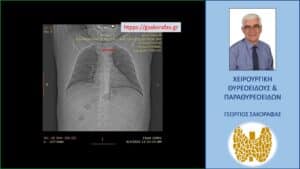

Αξονική τομογραφία – τοπόγραμμα. Εμφανής η απώθηση – απόκλιση της τραχείας (κόκκινο βέλος) προς τα δεξιά λόγω πίεσής της από τον διογκωμένο καταδυόμενο αριστερό λοβό.